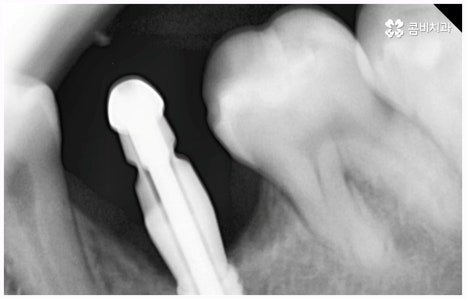

임플란트 종류 는 환자분들의 상황에 따라 달라지기 때문에 먼저 꼼꼼하게 정밀 검진을 받아보고 숙련된 의료진과 충분히 상담을 해 볼 필요가 있습니다. 환자분들의 치아 및 잇몸과 뼈의 상태, 전신 건강 등을 종합적으로 살펴보고 만약 필요하다면 선행 치료부터 받게 될 거예요. 선행 치료는 보통 임플란트 식립을 하게 된 치아 상실의 원인, 그리고 치아가 상실된지 얼마나 오랜 시간이 흘렀는지 여부에 따라 달라지는데 예를 들어 비교적 어린 나이에 큰 사고를 당해서 치아를 잃게 되었을 때 지체없이 바로 치과로 내원한 경우, 잇몸뼈가 건강하고 나이 등 회복력에 대한 기대치도 높은 편이며 다른 전신 질환, 상용약 등 잇몸에 지속적인 영향을 줄 만한 요소가 없다고 한다면 별다른 선행치료 없이 임플란트 종류 중 당일 심고 바로 임시 치아로 식사를 할 수 있는 원데이 임플란트를 통해 보다 빠르고 간편한 수복을 할 수 있어요.

보통은 인공 치근을 식립한 후에 얼마 동안 시간을 두어 골유착이 잘 일어나게 한 후에 지대주(연결 부위)를 연결하고 크라운 보철물을 제작, 장착해 주는데 여기서 개개인의 상황이 모두 다르기 때문에 회복 기간이 얼마나 걸릴지 정확하게 알 수는 없지만 대부분 3~6개월 정도라고 보면 될 거예요. 그동안은 불편한 상태로 사용을 할 수 밖에 없는데 만약 검진 및 발치, 식립, 임시 치아 제작 및 장착까지 모두 하루 만에 이루어진다면 임플란트 치료 기간을 줄일 수 있을 뿐 아니라 내원 횟수 및 통증과 불편감 또한 감소시킬 수 있을 것이기 때문에 시간적인 여유가 많지 않은 직장인분들, 학생들, 유학생분들이나 지방에 거주하시는 분들과 같은 경우에 임플란트 종류 중 원데이 임플란트 식립에 대해서 관심을 많이 보이고 있습니다. 그러나 말씀드린 것처럼 누구나 받을 수 있는 것은 아니기 때문에 먼저 잇몸뼈의 상태를 꼼꼼하게 체크하여 가능성 여부를 알아볼 필요가 있으니 검진 및 상담부터 진행해 보시길 권유드리고 있어요.